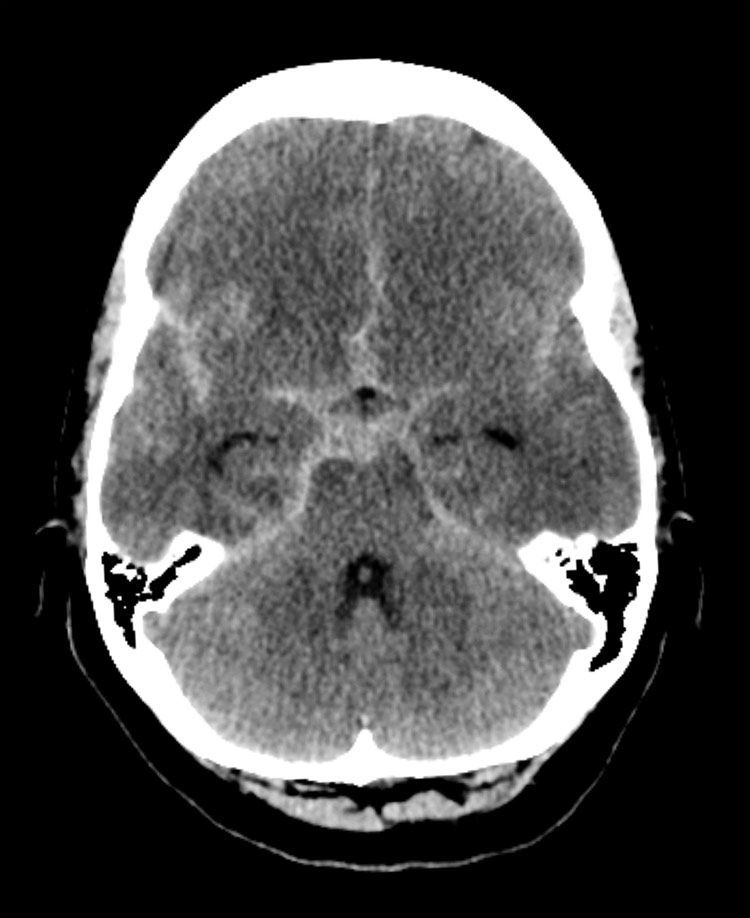

@RadMasterclass

Radiology Masterclass

2 days

CT BRAIN QUIZ: Non-contrast CT Brain: Sudden onset severe headache. What does the image show? A: Subdural haematoma B: Subarachnoid haemorrhage C: Intraventricular haemorrhage D: Extradural haematoma E: Intracerebral haemorrhage Start Quiz https://t.co/ATFl8YktNe

34

16

132